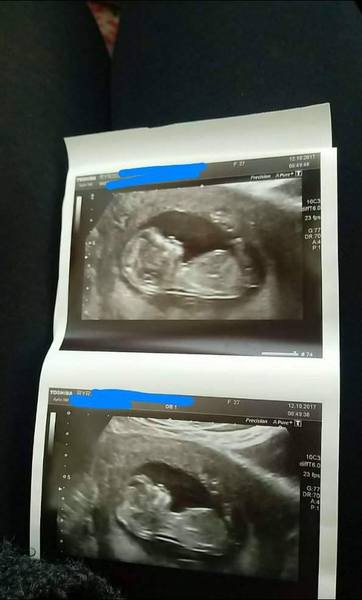

We had our scan today, all went well and we are having a little boy!

Yeah it was a private scan as I am only 16 weeks. We have a really good offer on where it's only £39 for the scan!

I never found out with DD, it's actually a bit weird knowing so early! But will be nice to organise the nursery and get some boy clothes!

Congrats MissYeti! Lovely pics. And Congrats on your little boy Sam!

We found out this evening, everything came back low risk and..... it's a Girl ! So excited!

We also had our scan today - we were the polar opposite and baby behaved beautifully, we were in and out in 15 minutes with everything done! Got to see everything, teeny tiny feet and hands, face, the works, it was amazing! Feel like I can start to relax & enjoy it all now.

Oh wow @Sam and @Aspenn we've one of each on the thread now. A great day! Lovely photos, you too @GlenaCoco. Glad baby was behaving!